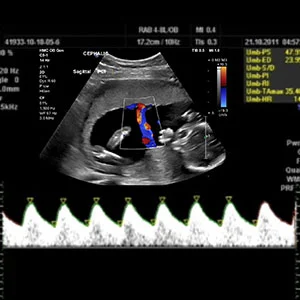

Doppler Scan

3D/4D Ultrasound